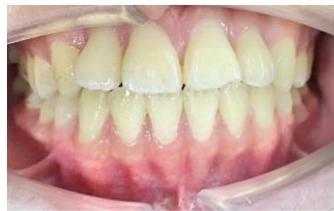

### b) Intraoral Examination

Intraoral examination revealed severe proclination and protrusion of both the maxillary and mandibular incisors [6]. The occlusal relationship was Class I at the canine (tooth 3) and first molar (tooth 6) levels bilaterally. A critical unfavorable biological factor was the proximity of the mandibular incisor roots to the labial cortical plate, representing a high-risk condition when planning extraction-based anterior retraction mechanics [10-12]. All four third molars were present.

Figure 2: Pre-Treatment Intraoral Photographs